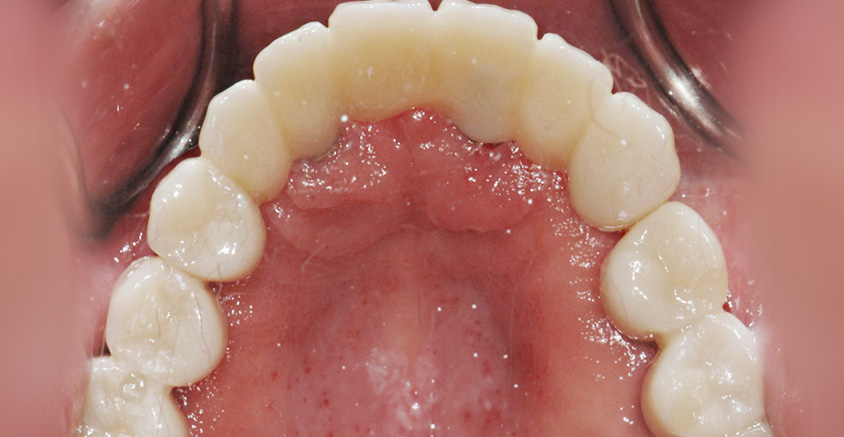

Before